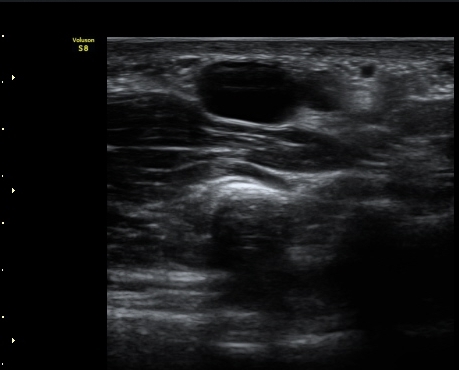

ÃÊÀ½ÆÄ °Ë»ç

¼Õ¸ñ(lunate ±âÁØ)°ú ¼ö±Ù°ü ±ÙÀ§ºÎ(scaphoid ±âÁØ) Á¤Á߽Űæ Ⱦ´Ü¸é°Ë»ç¿¡¼­ Á¤»óÀûÀÎ

¸ð¾çÀ¸·Î °üÂûµÈ´Ù(±×¸² 1, 2).